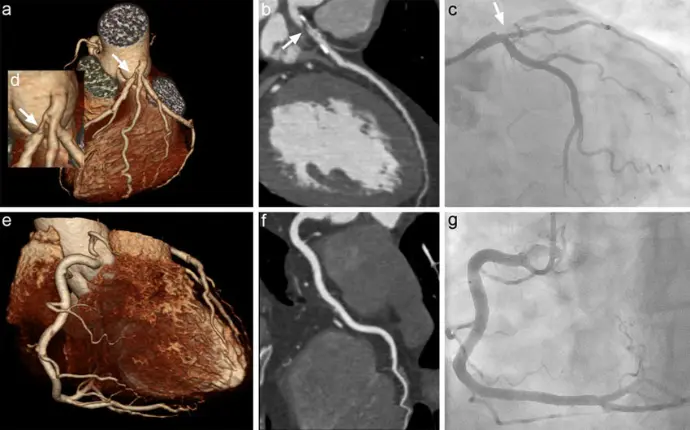

CT. CORONARY ANGIOGRAPHY

CT Coronary Angiography is a non-invasive, fast, and highly accurate scan that creates detailed 3D images of your heart’s arteries. It helps detect blockages, narrowing, and heart abnormalities without inserting any tubes or catheters.